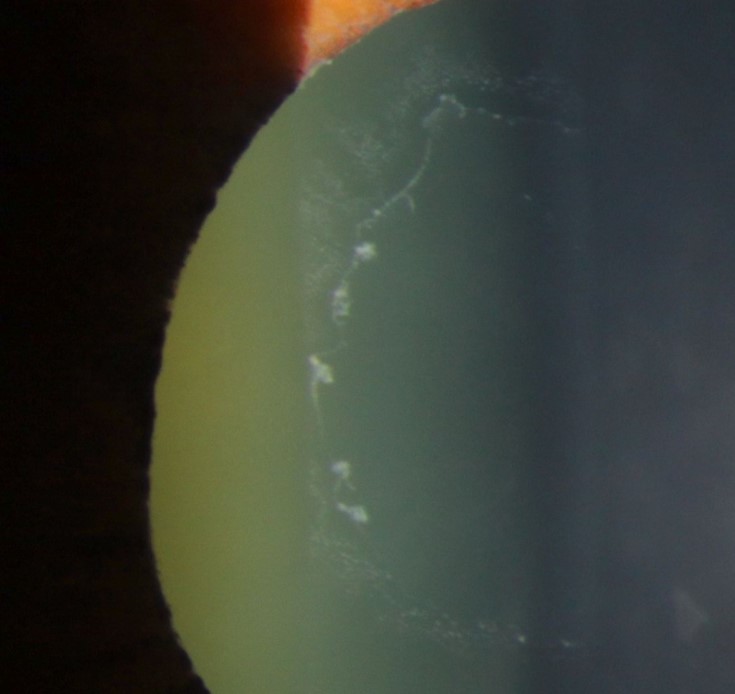

Image 3 illustrates extensive endothelial pigment deposition that is associated with PXF syndrome.